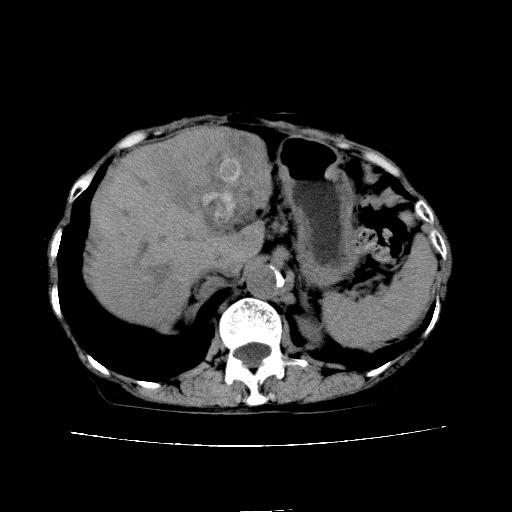

延迟期

看片子胆管里结石,肝上显示的占位会不会是胆管癌?大家帮忙看看,图像不太好,手头的处理文件没有,大致转换了一下,有原始图像数据

胆管细胞癌,胃壁增厚

支持胆管细胞癌诊断,胃壁增厚。